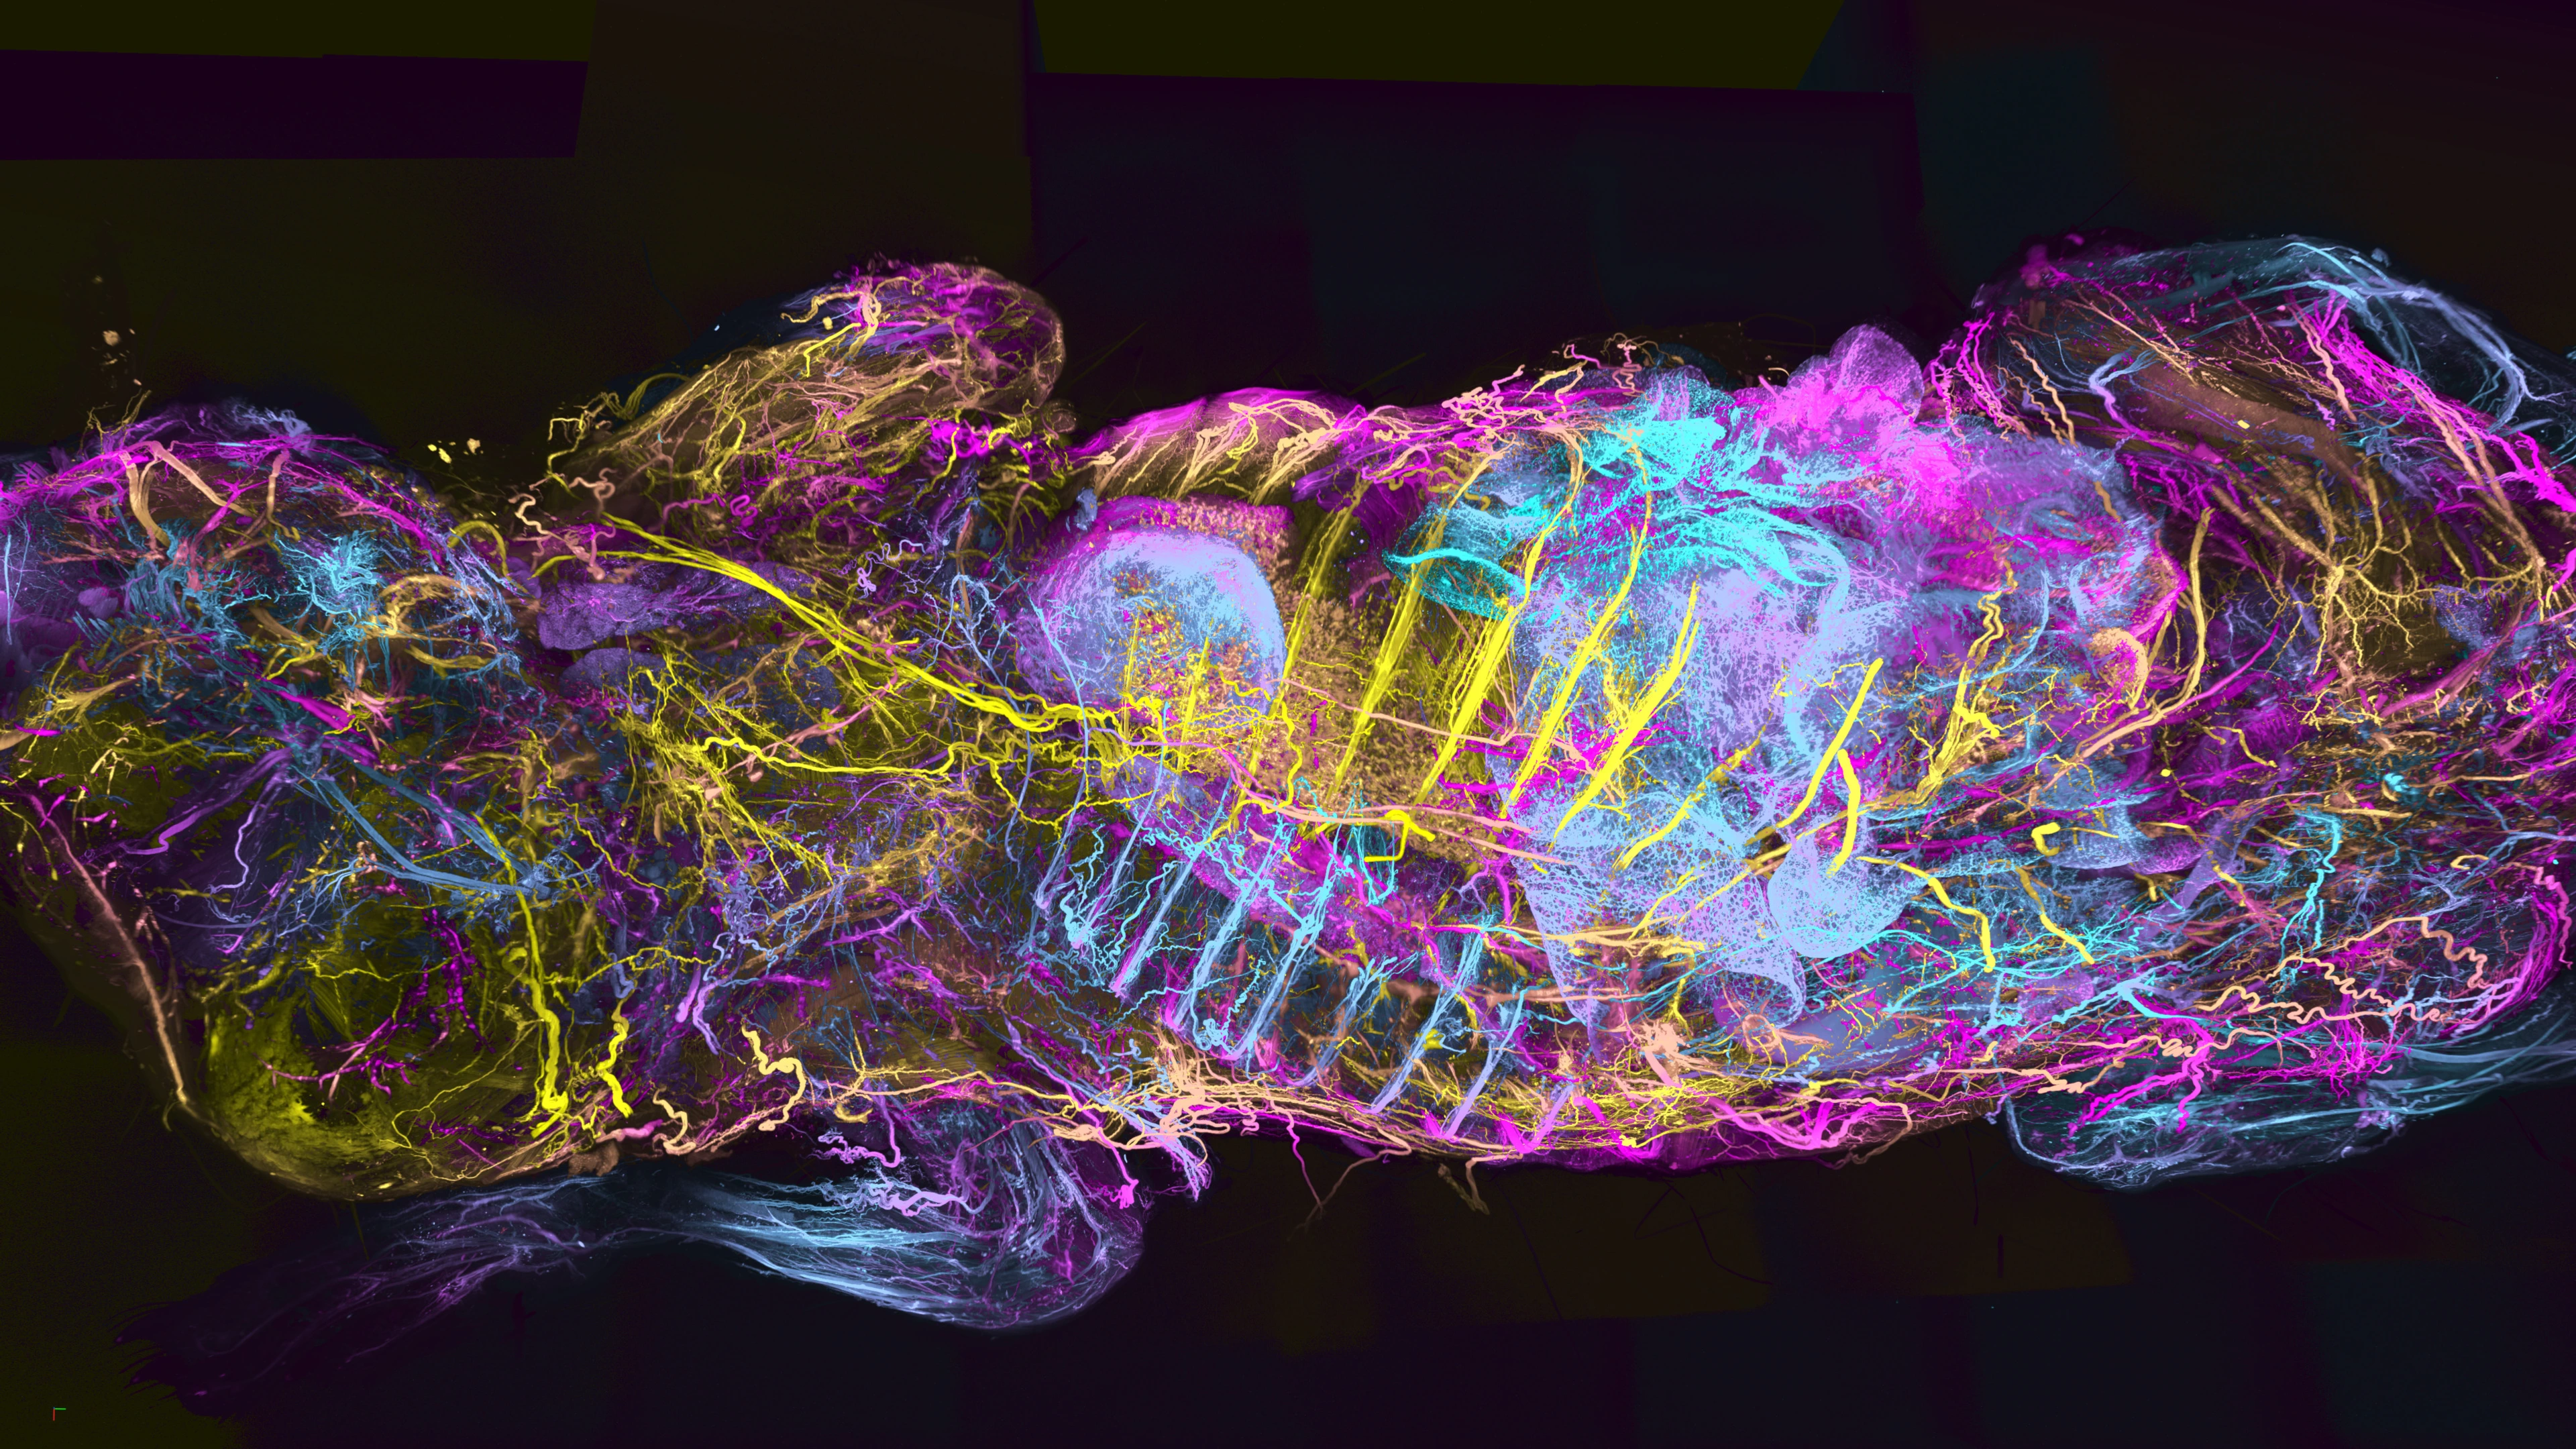

Ganzkörperkarte des Nervensystems einer Maus.